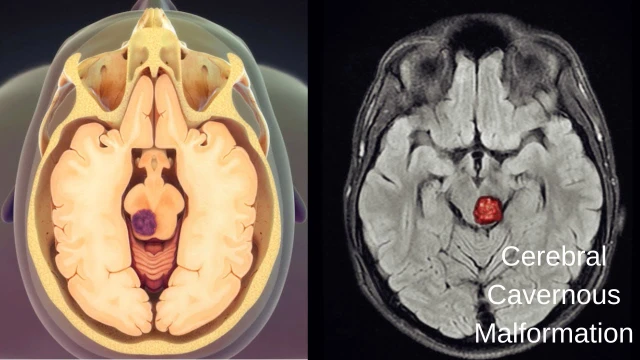

Các bệnh thần kinh - tinh thần